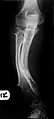

Múltiples osteocondromas que causan deformidad del antebrazo (acortamiento del radio con arqueamiento secundario del cúbito ).